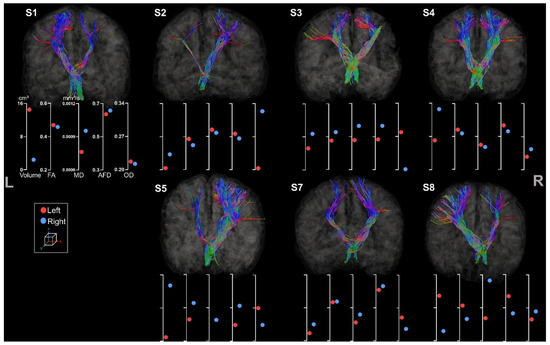

3.3.2. Fronto-Ponto-Cerebellar Tracts

3.3.3. Cerebello-Thalamo-Frontal Tracts